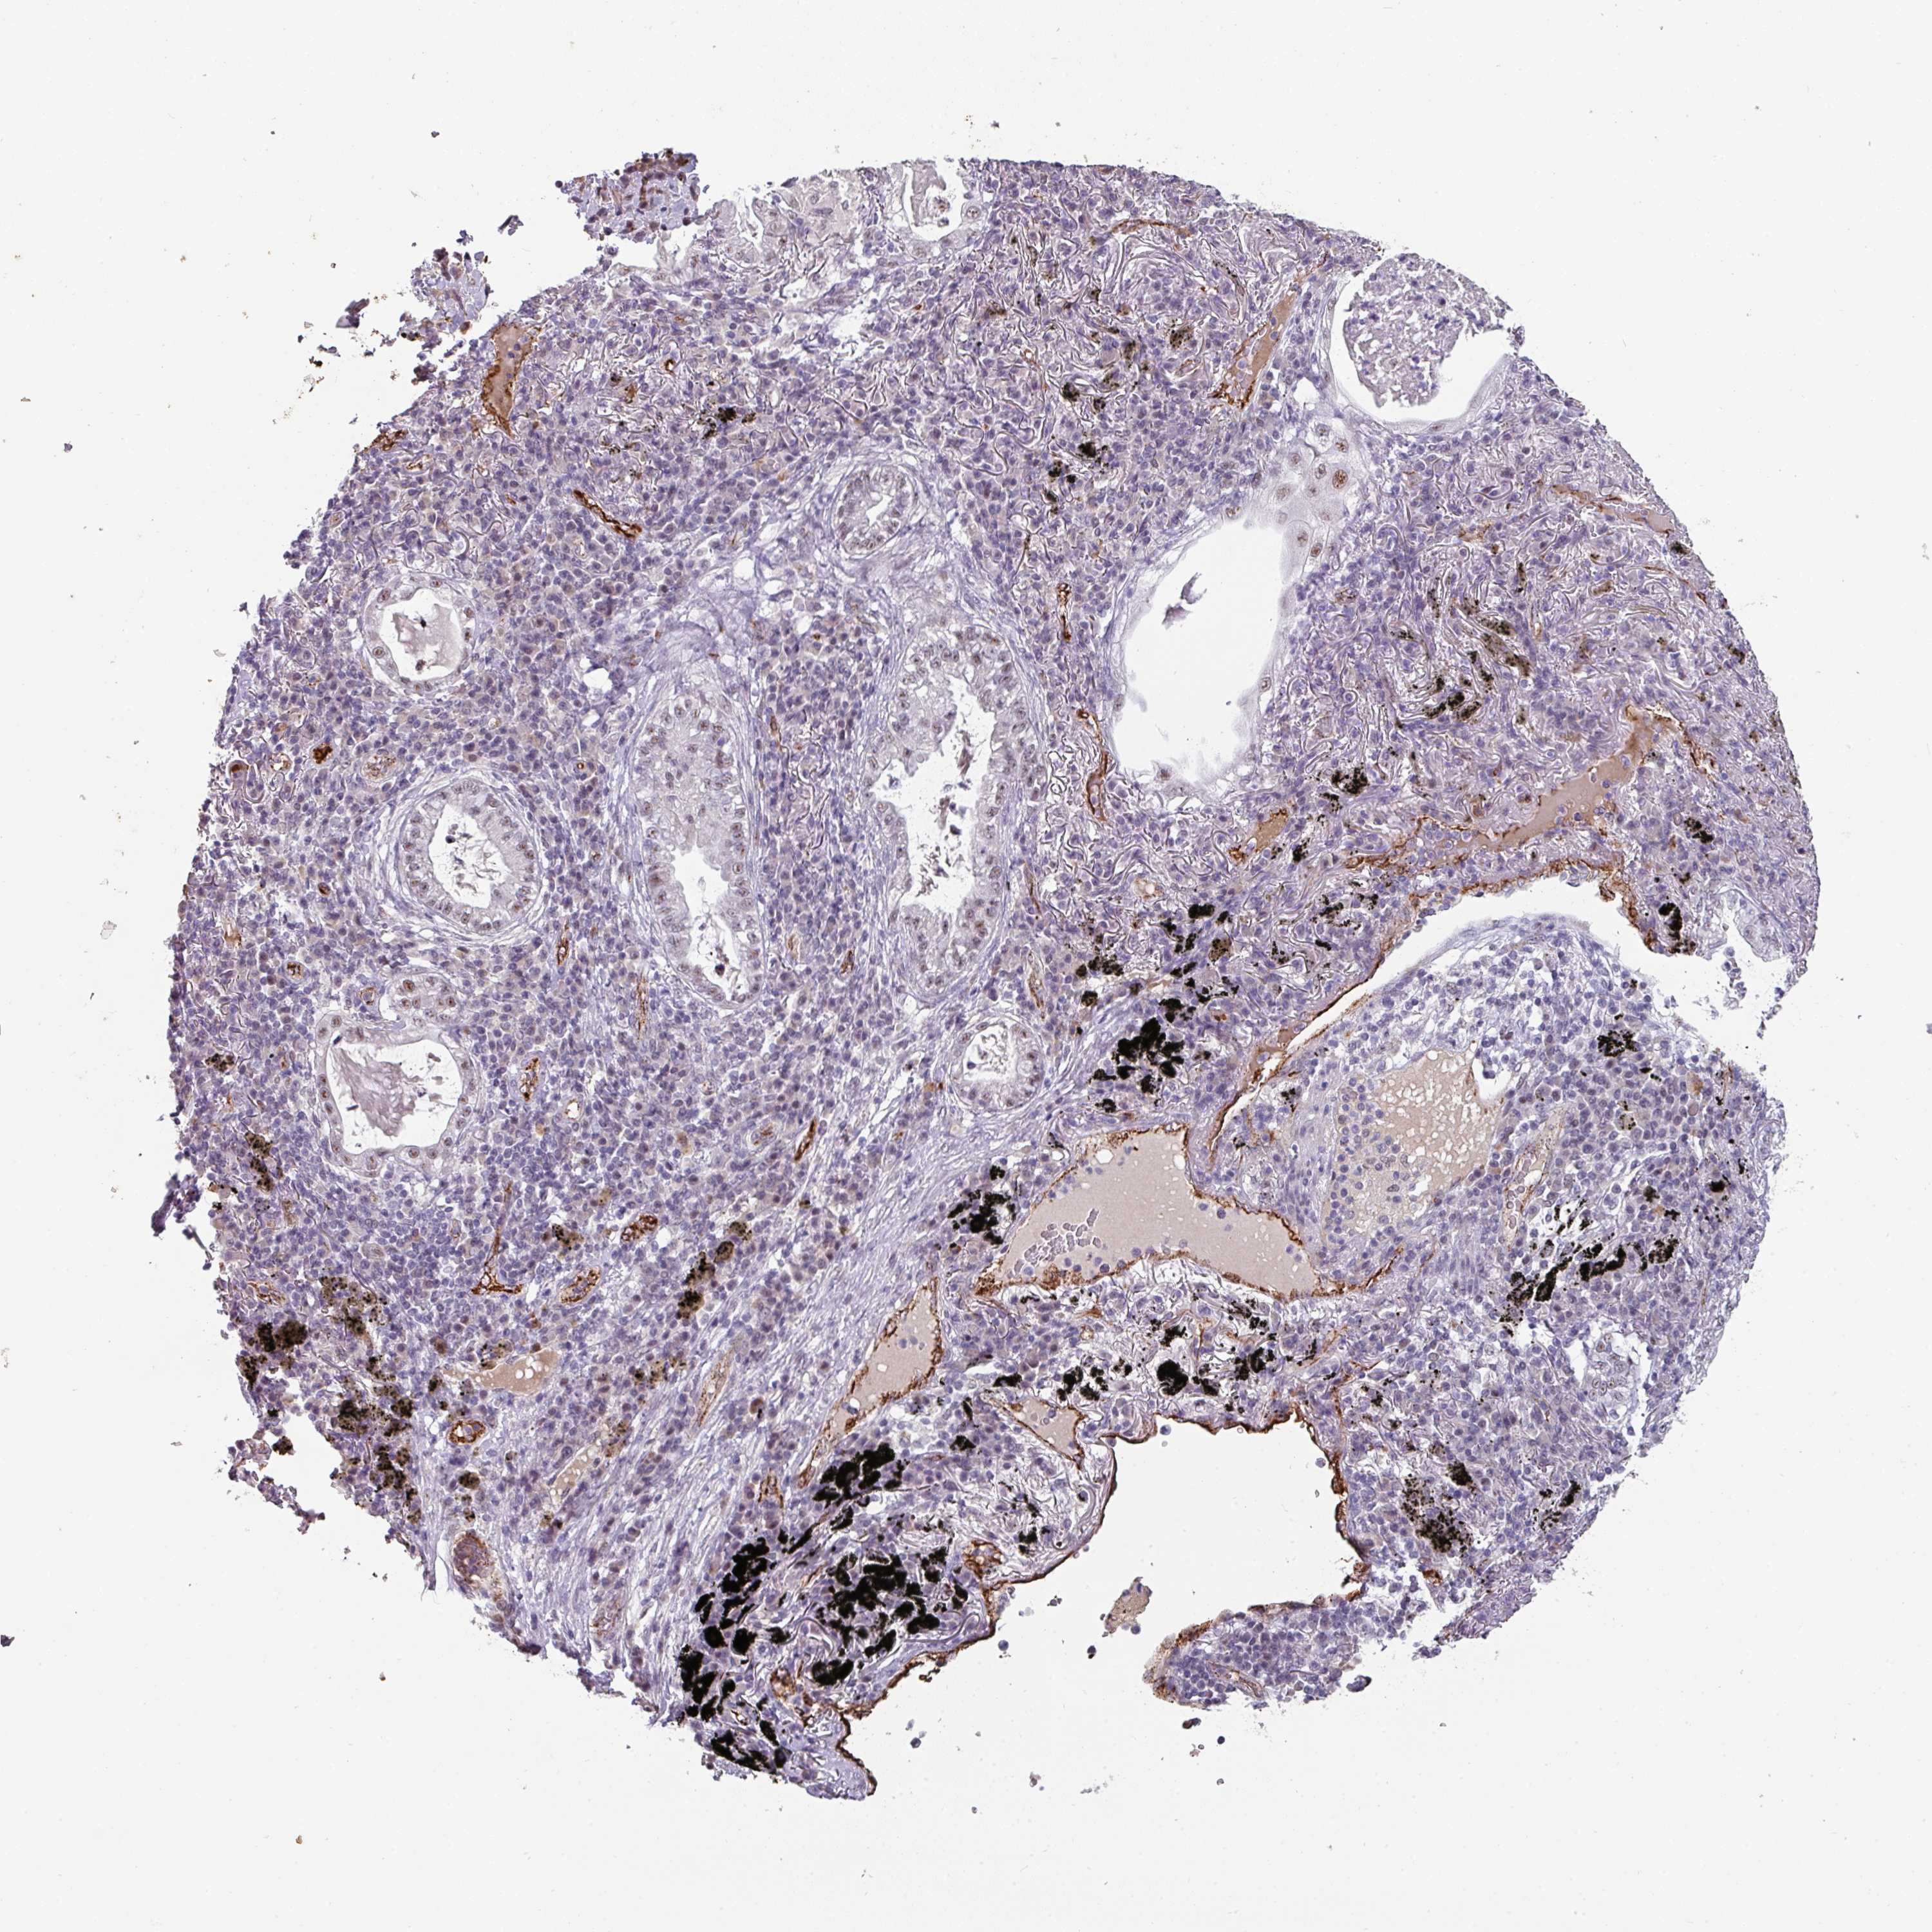

CANCER LUNG CANCER Show tissue menu

LUNG ADENOCARCINOMA (TCGA) - Interactive survival scatter ploti

The Survival Scatter plot shows the clinical status (i.e. dead or alive) for all individuals in the patient cohort, based on the same data that underlies the corresponding Kaplan-Meier plots. Patients that are alive at last time for follow-up are shown in blue and patients who have died during the study are shown in red.

The x-axis shows the expression levels (FPKM) of the investigated gene in the tumor tissue at the time of diagnosis. The y-axis shows the follow-up time after diagnosis (years). Both axes are complimented with kernel density curves demonstrating the data density over the axes. The top density plot shows the expression levels (FPKM) distribution among dead (red) and alive patients (blue). The right density plot shows the data density of the survived years of dead patients with high and low expression levels respectively, stratified using the cutoff indicated by the vertical dashed line through the Survival Scatter plot. This cutoff is automatically defined based on the FPKM cutoff that minimizes the p-score. The cutoff can be changed by dragging the vertical line or by entering a cutoff value in the square labeled "Current cut-off".

Under the Survival Scatter plot the p-score landscape (black curve; left axis) is shown together with dead median separation (red curve; right axis). Dead median separation is the difference in median mRNA expression between patients who have died with high and low expression, respectively. It is calculated as follows: median FPKM expression of dead patients with high expression - median FPKM expression of dead patients with low expression. This is intended to aid the user in visually exploring custom cutoffs and the associated p-scores and dead median separation.

Individual patient data is displayed and can be filtered by clicking on one or more of the category buttons on the top of the page. Categories describing expression level and patient information include: high, low, alive, dead, female, male and tumor stages. The scale of the x-axis can be toggled between linear and log-scale by clicking on the "x log" button. Mouse-over function shows TCGA ID, patient information and mRNA expression (FPKM) for each patient.

& Survival analysisi

Kaplan-Meier plots summarize results from analysis of correlation between mRNA expression level and patient survival. Patients were divided based on level of expression into one of the two groups "low" (under cut off) or "high" (over cut off). X-axis shows time for survival (years) and y-axis shows the probability of survival, where 1.0 corresponds to 100 percent.

SIDT2 is not prognostic in Lung Adenocarcinoma (TCGA)

Best expression cut offi

: 25.27

P scorei

N/A

TCGA RNA samplesi

RNA-seq data is reported as average FPKM (number Fragments Per Kilobase of exon per Million reads), generated by the The Cancer Genome Atlas (TCGA) .

Normal distribution across the dataset is visualized with box plots, shown as median and 25th and 75th percentiles. Points are displayed as outliers if they are above or below 1.5 times the interquartile range. FPKM values of the individual samples are presented next to the box plot.

Average pTPM 21.9

Number of samples 497